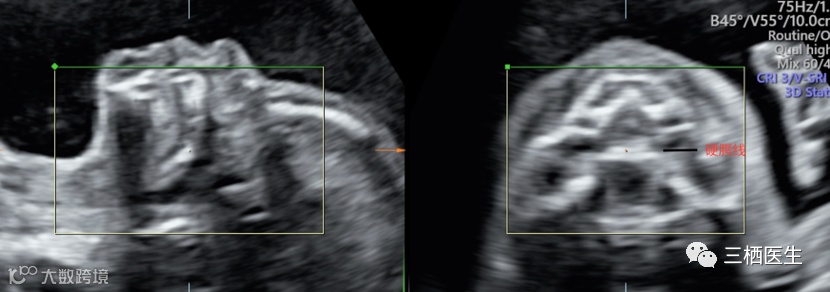

2.软腭线(如果软腭是好的,前面的硬腭也是好的)

完整的软腭线

3.软腭如果异常,再往前看硬腭线,由此确定单纯腭裂的程度。

完整的硬腭线

下图可见硬腭线回声中断:

上述几个切面,最容易扫描的是硬腭线,常常作为筛查严重单纯腭裂的平面。